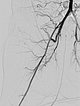

In the control DSA, the main part of the tumor has now been successfully embolized and cut off from the circulation. Only very cranial tumor-supplying branches remained at this stage of the embolization.

These very cranial parts are now also catheterized super-selectively with the microcatheter and embolized with particles. For better navigation of the microcatheter, the vessels from a previous injection are electronically overlaid by the computer (so-called “overlay display”, white in the image).